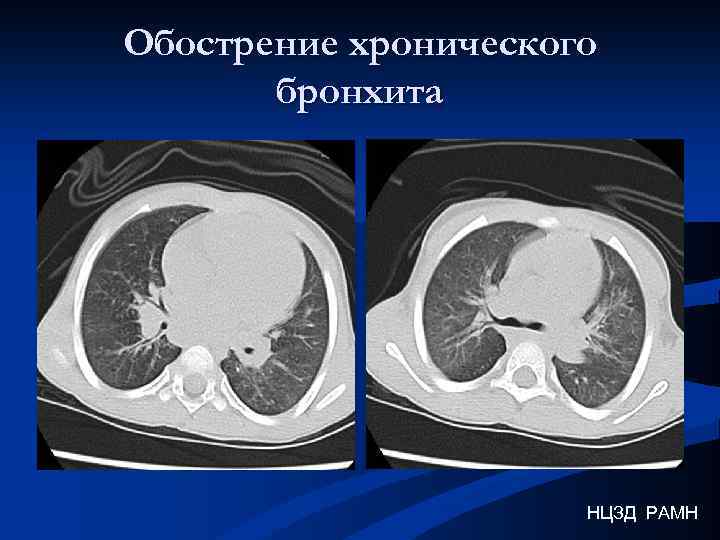

Обострение хронического бронхита НЦЗД РАМН